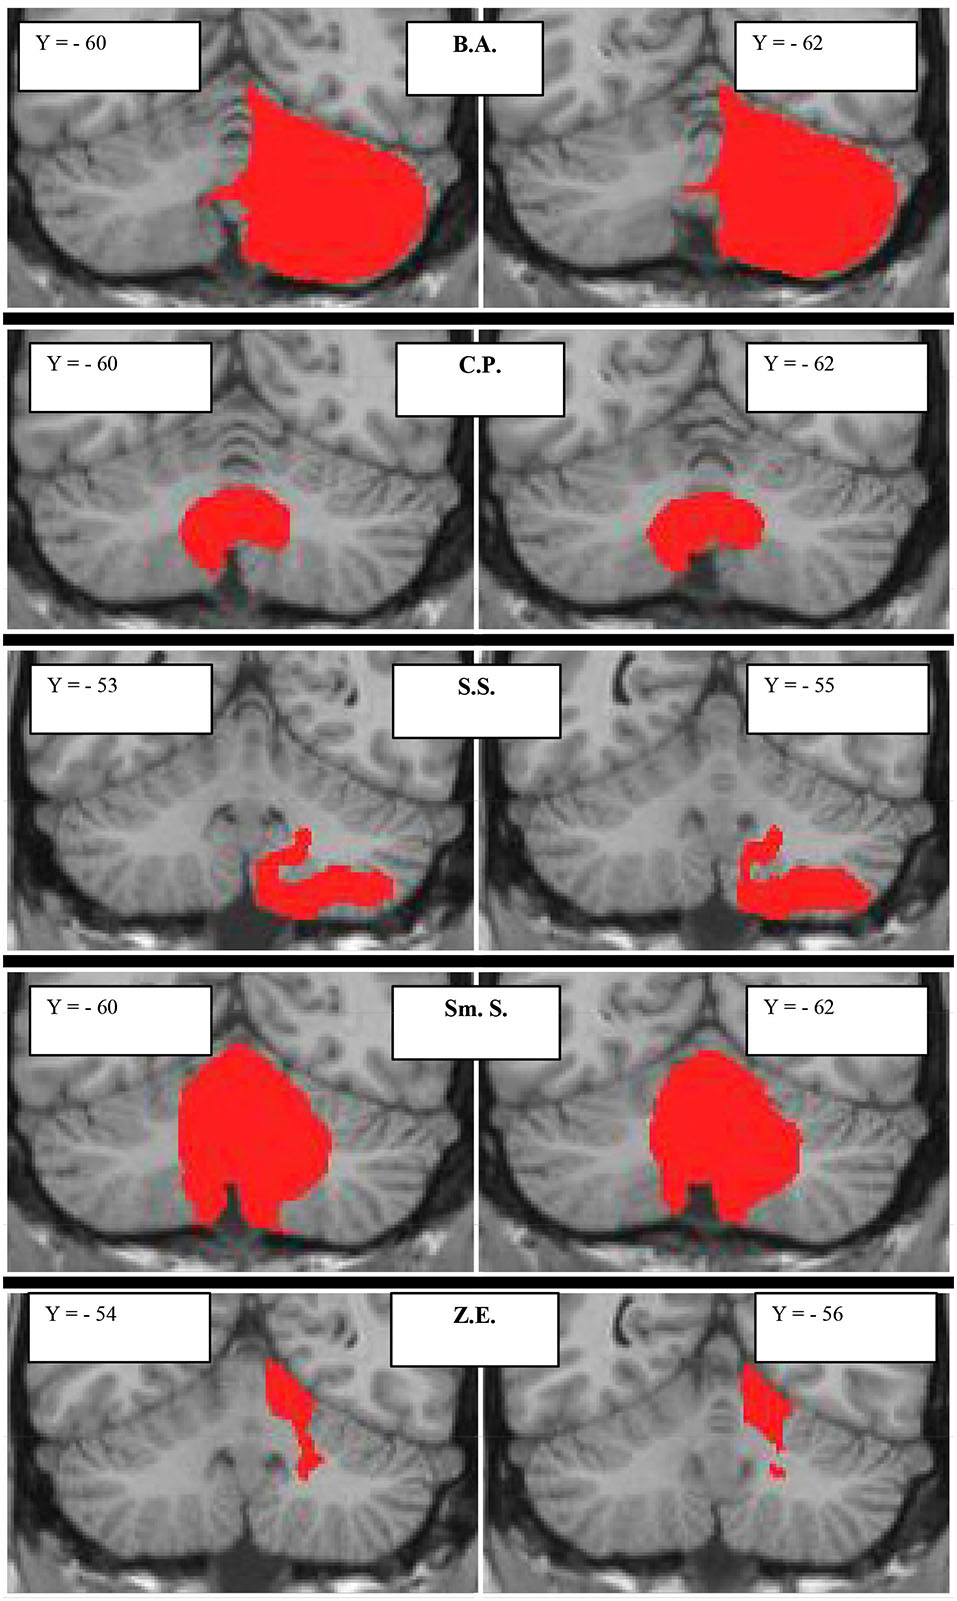

The lesion characteristics of patients with focal damage, according to the MRI images, are described in Figure 1 and Table 2.

Figure 1. Subjects with focal cerebellar lesions. Lesion extensions were assessed on 3D-T1-MPRAGEs after spatial normalization and overlaid onto a coronal T1-weighted template from Schmahmann et al. (2000). For each subject, the lesion is shown in two representative coronal sections. The case code is as in Table 2.